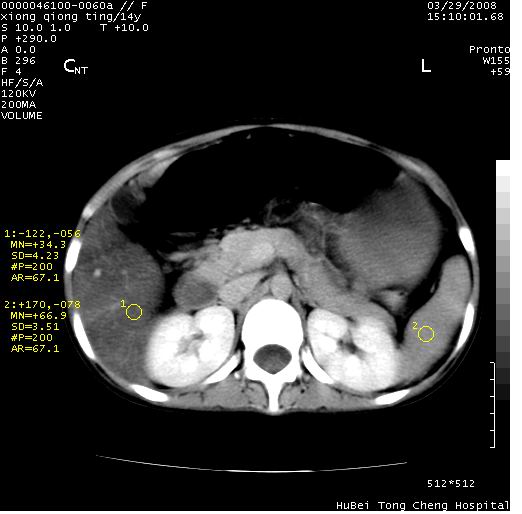

中下腹及盆腔ct轴位平扫+增强扫描(层厚10mm,螺距1.0,重建间隔10mm),图像如下:

(注:患儿检查当日上午9时口服胃肠道对比剂,下午3时许行ct扫描检查,未行对比剂直肠保留灌肠,检查当日患儿腹泻)

中下腹及盆腔ct轴位扫描(ps+ce)提示:腹部肠管明显充气扩张,并见数个不同宽度之气液平面;疑不全性肠梗阻或肠郁张。临床会诊考虑为患儿腹泻,肠郁张所致;后来未经特殊处理,患儿大便恢复正常,亦无腹胀。

临床出院诊断:1)结核性腹膜炎。2)腹膜后淋巴结结核。3)脂肪肝。